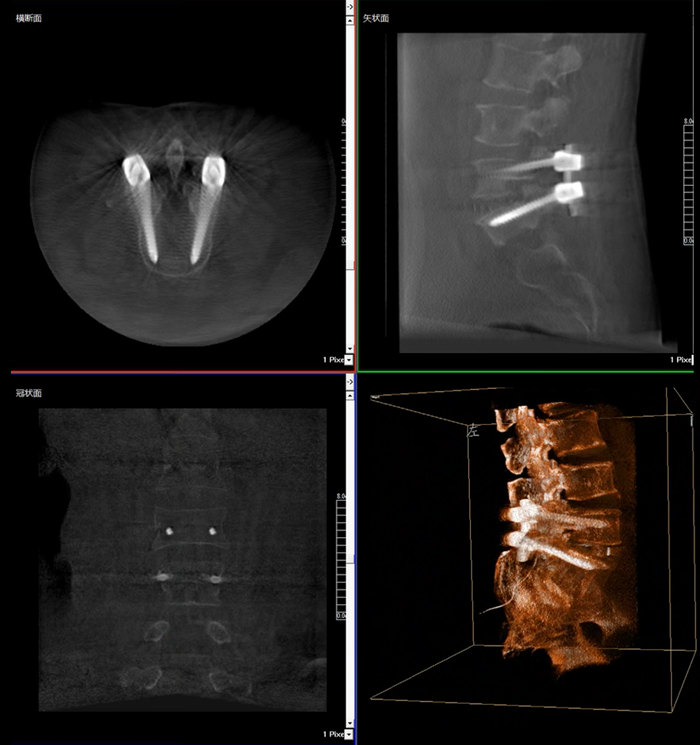

移動式三維C形臂,又稱骨科三維C臂,就是將傳統二維與“類CT模式”相結合的升級版C形臂,能在術中快速地生成橫斷面、矢狀面、冠狀面斷層圖像和三維立體圖像。通過不同方位的斷層圖像,能夠更清晰、完整地顯示椎體及其附件的解剖學結果,直觀地分析病變與周圍組織的立體空間關系,三維斷層成像能夠使手術模擬和手術方案的制定更加準確。

術中三維影像

而三維影像的MPR圖像組可以通過不同平面的切分,使成像區內更豐富的信息得以呈現。尤其是二維影像無法涉及的橫斷面,提供了另一個空間維度的信息量。

在MPR圖像中,冠狀面、矢狀面和橫斷面的信息大大提高了醫生對于病灶區以及手術效果的判定。

近年來,機器人導航設備在臨床的應用越來越廣泛,而三維影像是機器人導航系統手術執行的基礎,具有地圖定位和效果檢驗的雙重作用,使手術執行更加準確,手術效果驗證更有保障。

普愛醫療在國內率先掌握三維成像技術,繼三維影增C臂后,又推出國產品牌等中心平板移動式三維C形臂——天弓 PLX7500 。天弓配備進口30cm×30cm尺寸動態平板,作為“術中CT”,在手術中快速生成類CT斷層圖像和立體三維圖像,為醫者提供更全面的圖像信息,能夠準確地觀察植入物的情況。如果您對這款移動式三維C形臂產品感興趣的話,可咨詢:400-025-6366。